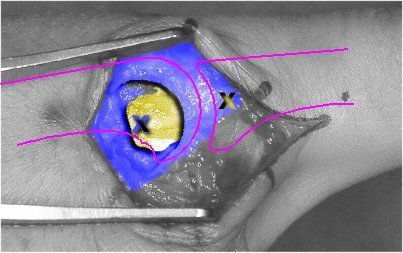

Surgery confirms the problem: the ulnar collateral ligament has extruded through a tear in the extensor tendon hood, and faces left, away from the joint.

The above picture has been colored to show the ligament (yellow), the hood (blue), and the two points which need to be connected back together (the "X"s). Without surgery, the tendon forms a layer which prevents the ligament from returning to its original position.